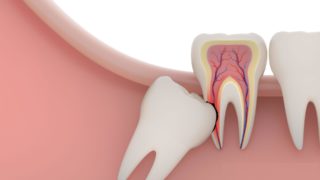

Gömülü olan dişler ağız içine sürme vakti gelmesine rağmen sürememiş, çene kemiği içinde kalmış dişlerdir. Sıklıkla 3. azı dişleri (yirmi yaş dişleri) gömülü kalmaktadır.

Gömülü dişler sıklıkla enfeksiyon kaynağı oldukları için ya da sağlıklı olan dişleri sıkıştırdıkları için çekilirler.